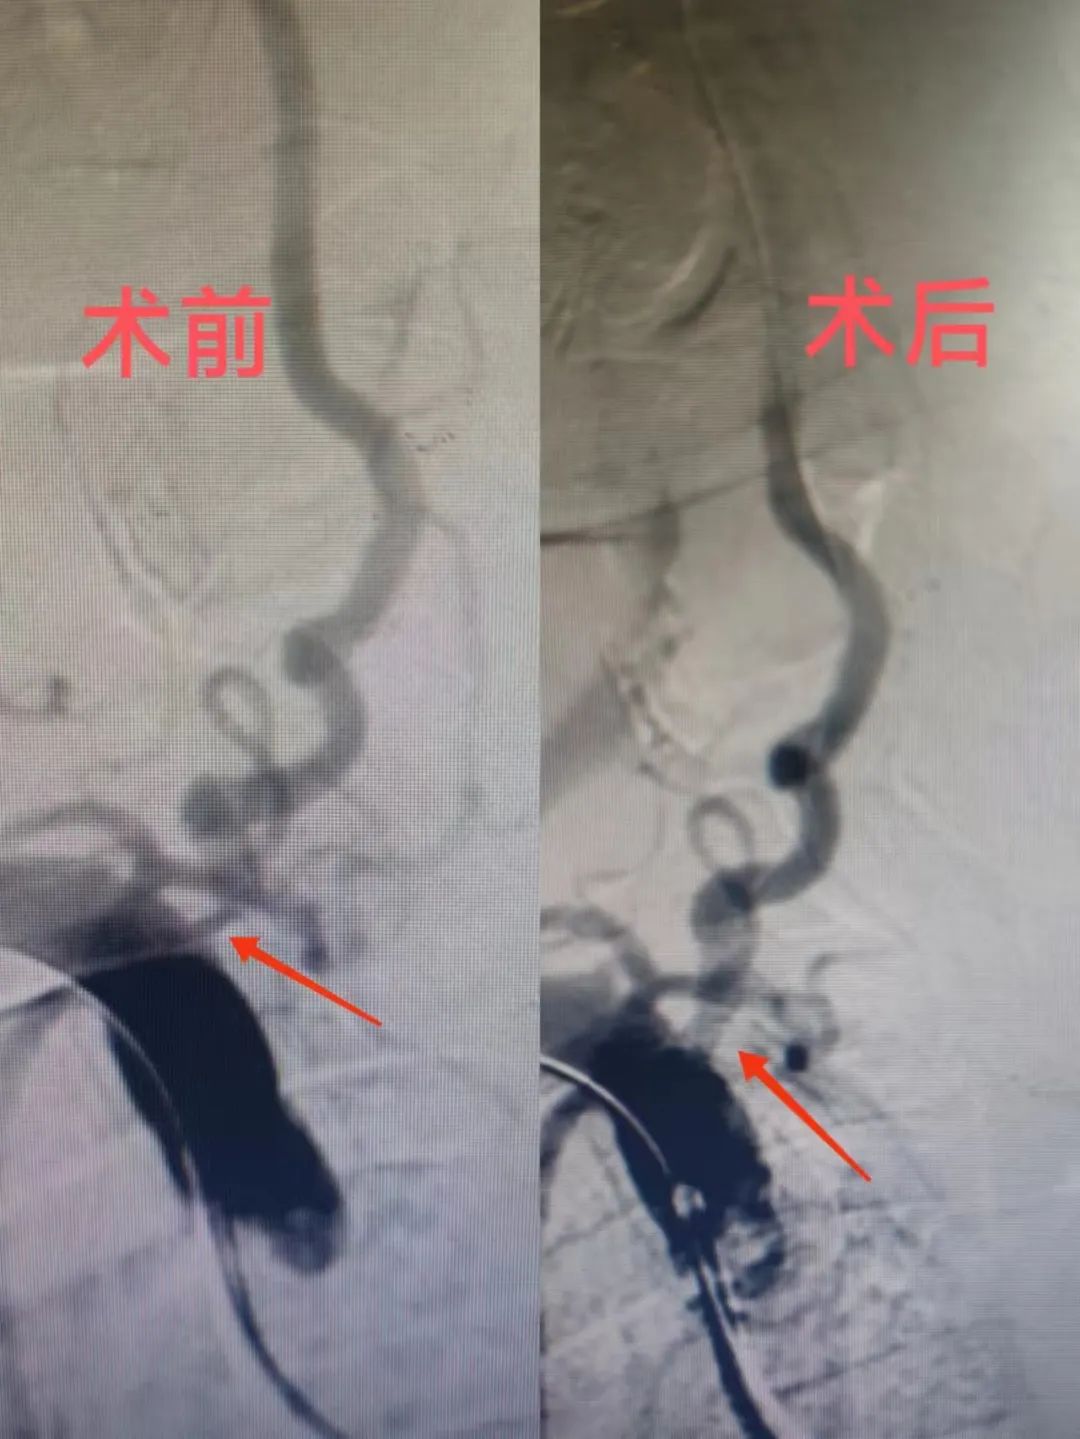

近日,葉大爺突然出現(xiàn)頭暈、右側(cè)肢體受限,家人以為葉大爺休息不好,在家靜臥一天后,病情仍沒有好轉(zhuǎn),于是立即將其送往北大醫(yī)療淄博醫(yī)院(淄博經(jīng)開區(qū)醫(yī)院)。神經(jīng)內(nèi)科醫(yī)師接診后,為其進行了詳細(xì)的檢查,經(jīng)頭頸部CTA檢查,發(fā)現(xiàn)腦部血管重度狹窄。為了進一步明確診斷,對其進了行腦血管造影檢查,結(jié)果發(fā)現(xiàn)狹窄程度非常嚴(yán)重,若不及時手術(shù),可能會造成腦梗死。

家屬得知神經(jīng)內(nèi)科主任鐘濤,接診過多例此類患者并痊愈出院,希望立即手術(shù)。鐘濤主任立即組織神經(jīng)內(nèi)科介入團隊對其進行會診,認(rèn)真研究該患者的病史及影像資料,最終決定為其手術(shù)。經(jīng)過完善的術(shù)前準(zhǔn)備,神經(jīng)內(nèi)科鐘濤主任、血管介入科主任劉綿春帶領(lǐng)介入團隊為其手術(shù),鐘主任憑借豐富的經(jīng)驗,克服重重難關(guān)順利為其放入支架,術(shù)后狹窄基本解除,患者無明顯不適感。術(shù)后患者癥狀緩解,返回病房,病人及家屬非常感激,向鐘濤主任、劉綿春主任及醫(yī)護人員表達了衷心的謝意。